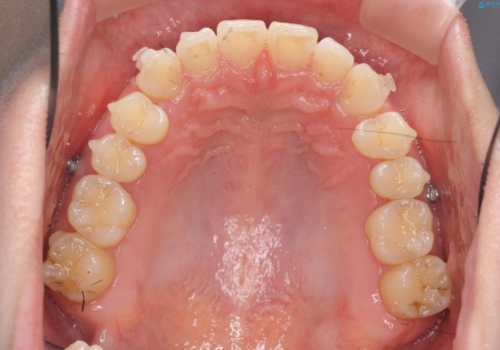

- 矯正装置

- インビザライン

- 1年10ヶ月

インビザラインを用いた治療計画を立て、しっかりと出っ歯を治すためにマイクロインプラントを併用します。

マイクロインプラントを併用することでしっかりとマウスピース全体を後方へ引き、前歯の突出感を改善することができました。